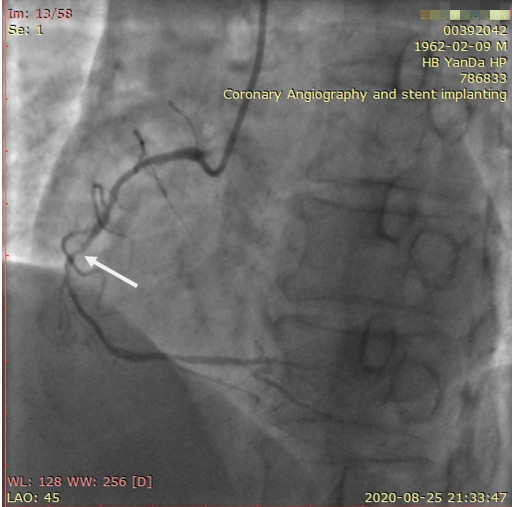

李先生右冠術(shù)后影像

手術(shù)方案確定之后,在心血管內(nèi)三科趙景新主任、介入醫(yī)學(xué)科富孝晨主任的配合下,翟光耀主任親自擔(dān)任主刀,分別依次對李先生的三支動脈進行了完全血運重建。由于手術(shù)進展順利,李先生術(shù)中沒有任何癥狀,耐受良好,于是成功的將三支動脈“一站式”治療!術(shù)中,由于李先生左主干遠(yuǎn)端分叉處存在嚴(yán)重病變,翟光耀主任選擇國際指南推薦的DK-mini-Crush技術(shù),確保了分叉處兩支主干開口均萬無一失。據(jù)悉,DK-mini-Crush技術(shù)是目前冠脈分叉病變領(lǐng)域最為復(fù)雜及難以掌握的介入技術(shù)之一,對手術(shù)醫(yī)生經(jīng)驗、體力均提出了極大的挑戰(zhàn)。極為擅長復(fù)雜介入技術(shù)的翟光耀主任卻用嫻熟的技術(shù)確保了李先生手術(shù)的成功。